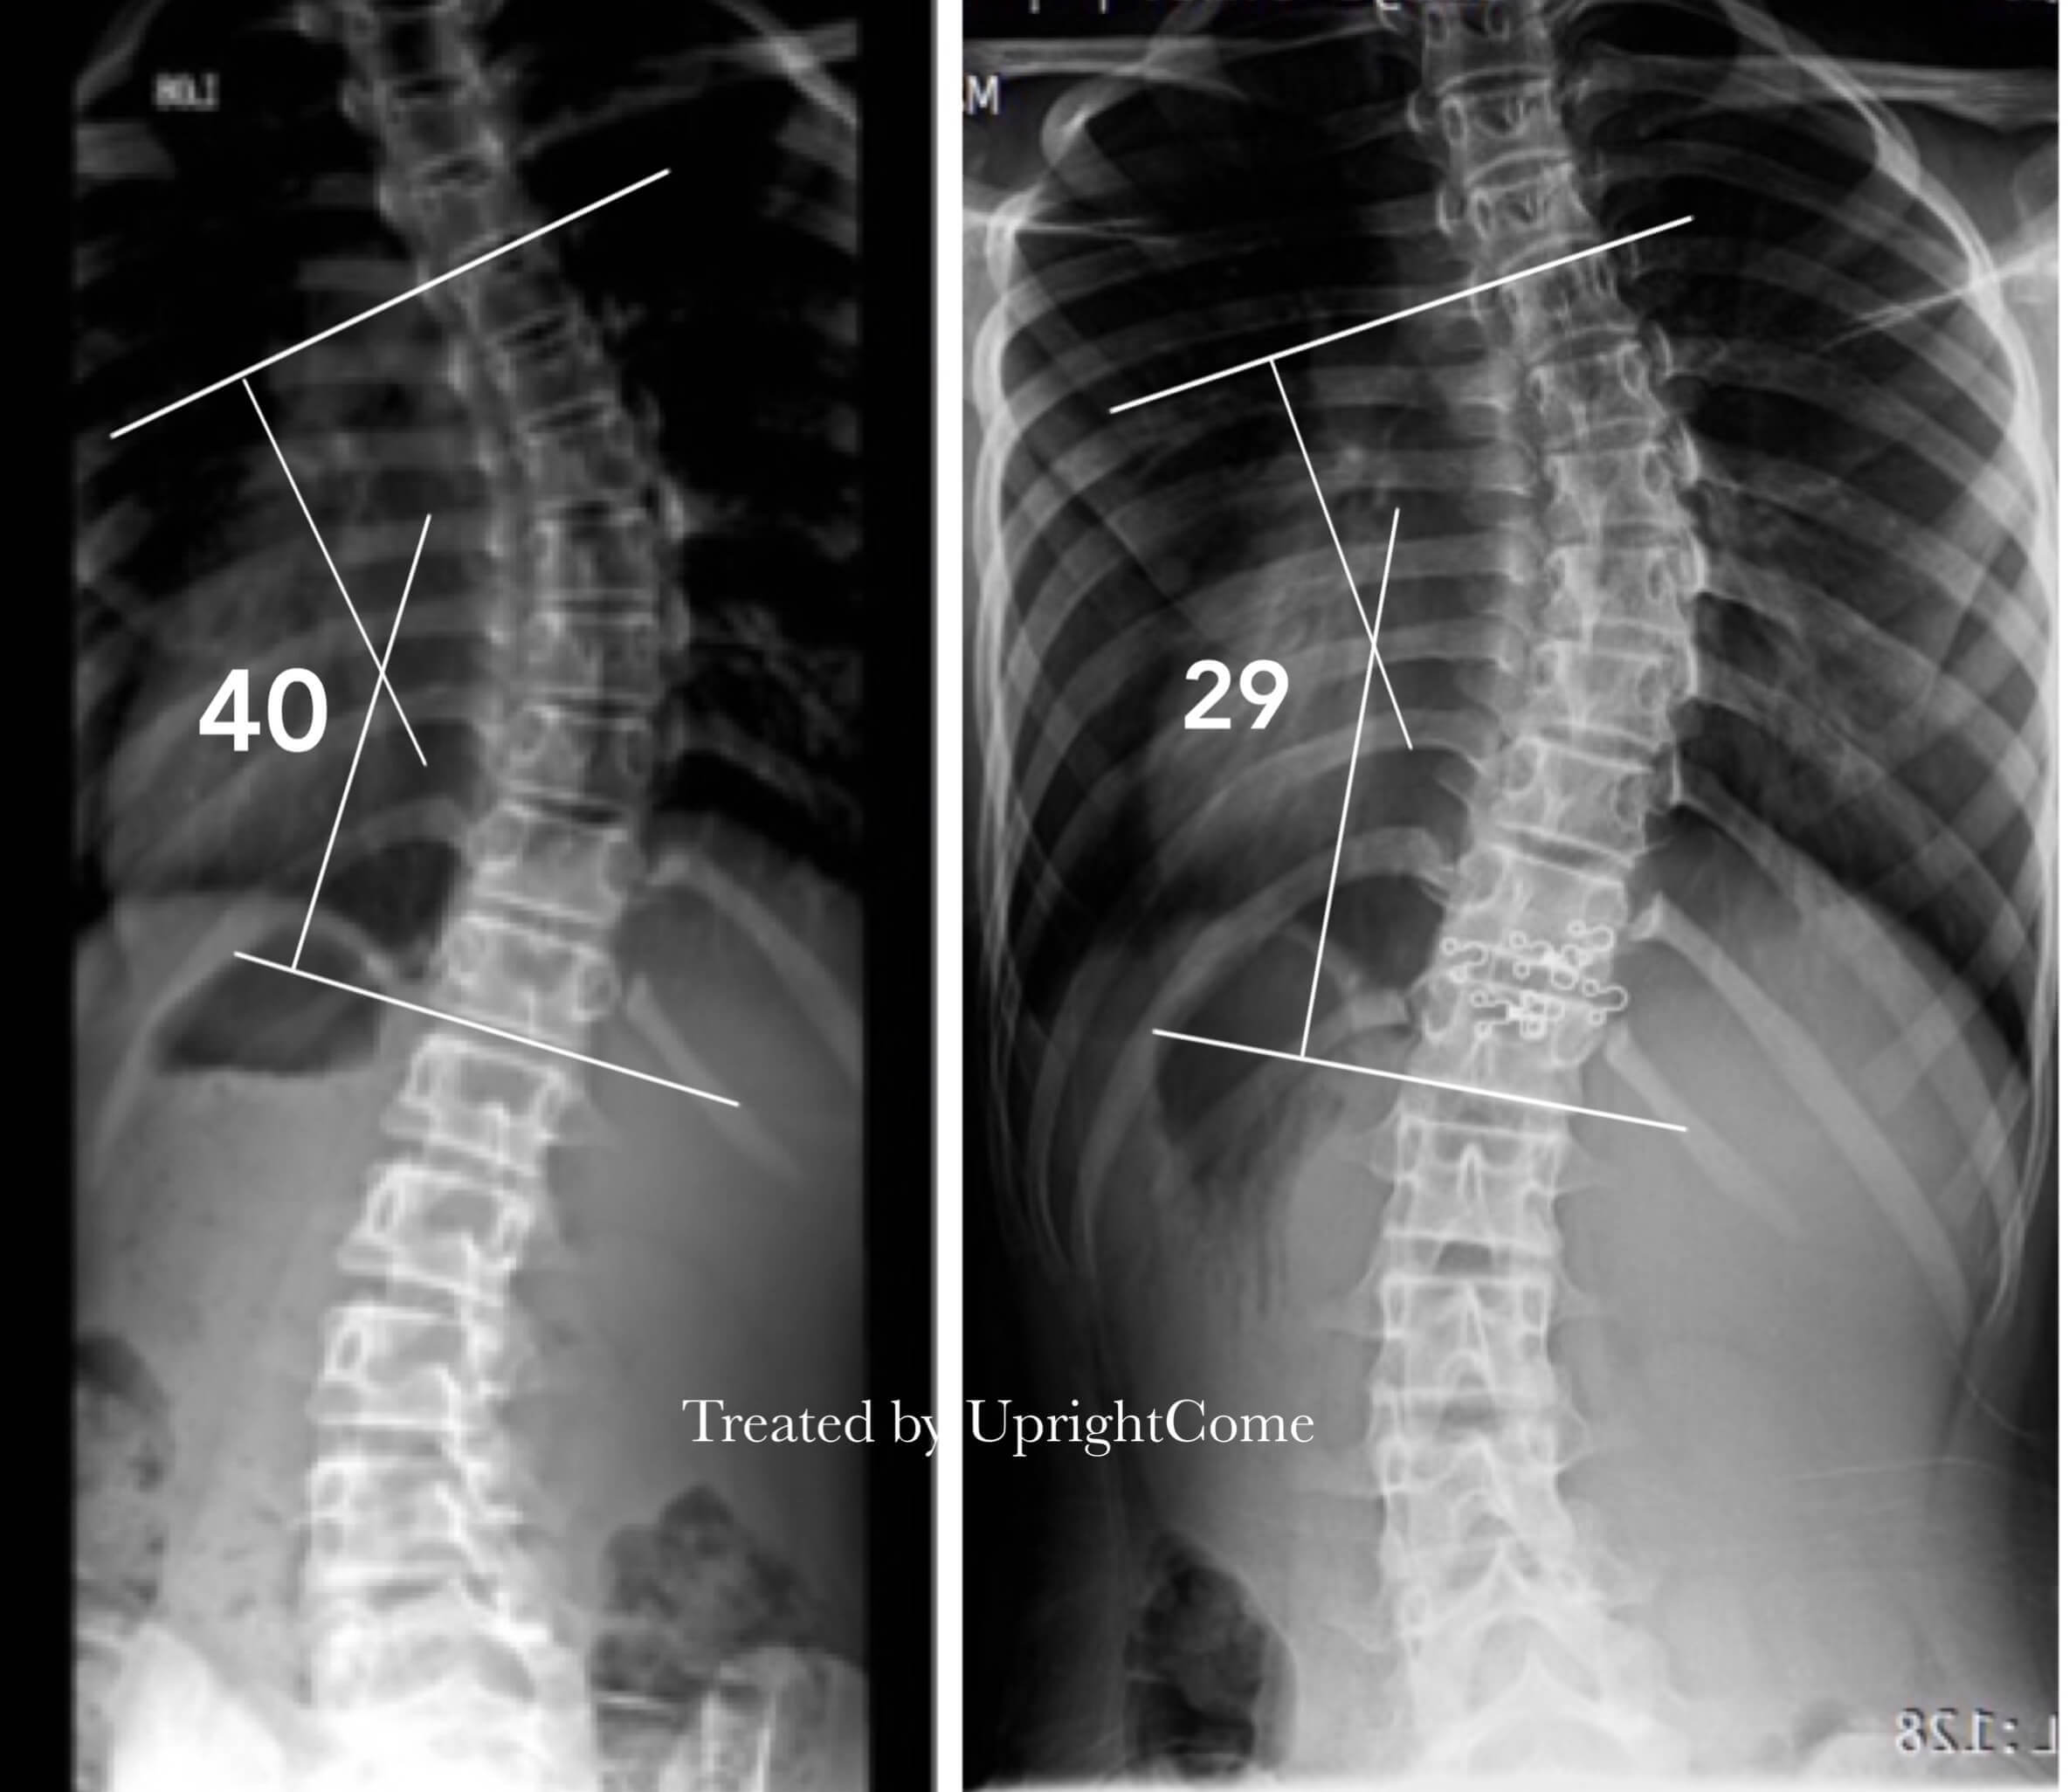

Case 8, 13 years old, 40° Cobb

![脊椎側彎患者經過側彎矯正治療後,胸椎角度由40度減少到29度。]()